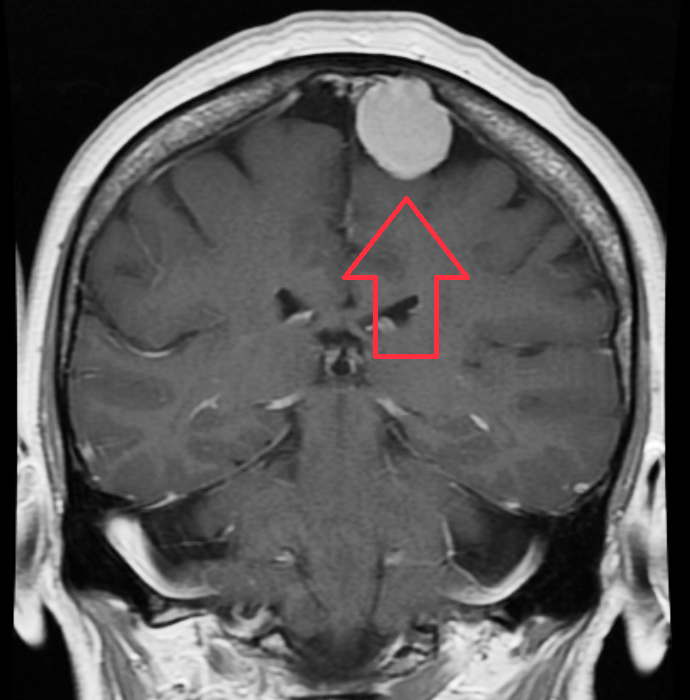

La epilepsia es una condición neurológica crónica que afecta a millones de personas en todo el mundo.